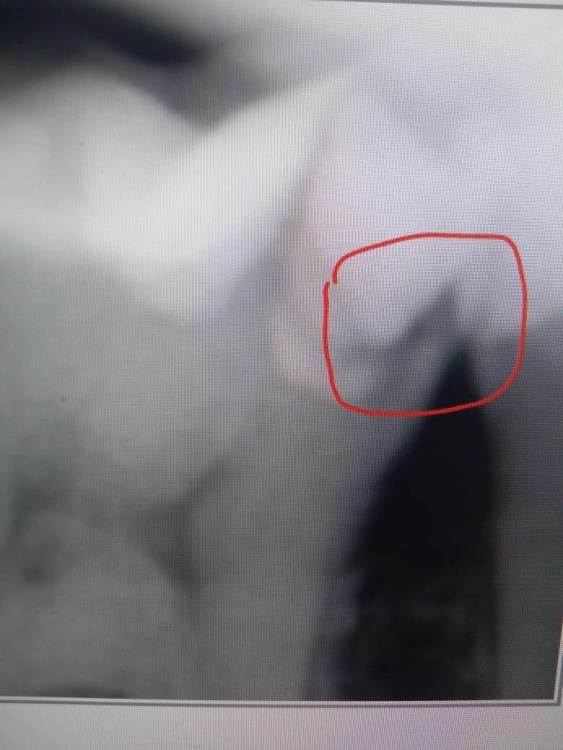

Aleksandr21321 Опубликовано 1 февраля, 2024 Поделиться Опубликовано 1 февраля, 2024 (изменено) Посмотрев на данные снимки, пользователи данного форума посоветовали сходить к стоматологу, ведь возможно тут вторичный кариес. (Снимки ниже) Я сходил к доку и вот диалог с ним: - Здравствуйте, стоматолог! Это вторичный кариес на снимках? - Сначла дам комментарий по поводу синего снимка. Пломба была поставлена в другом месте, не у нас. У вас зуб разболелся и я просто открыл каналы и удалил нерв и закрыл шахту обратно. Там я не высверливал потому что визуально смысла не было. Там все герметично переживать не о чем - А что по поводу серого снимка, доктор? - Я зачистил до плотных тканей и поставил пломбу. Ничего страшного Скажу честно, я мало что понял из диалога со стоматологом. Кариес это или нет - это вопрос, который все еще меня тревожит. Как думаете, надо искать нового дока или нынешний прав и беспокоиться не стоит? Изменено 1 февраля, 2024 пользователем Aleksandr21321 Ссылка на комментарий